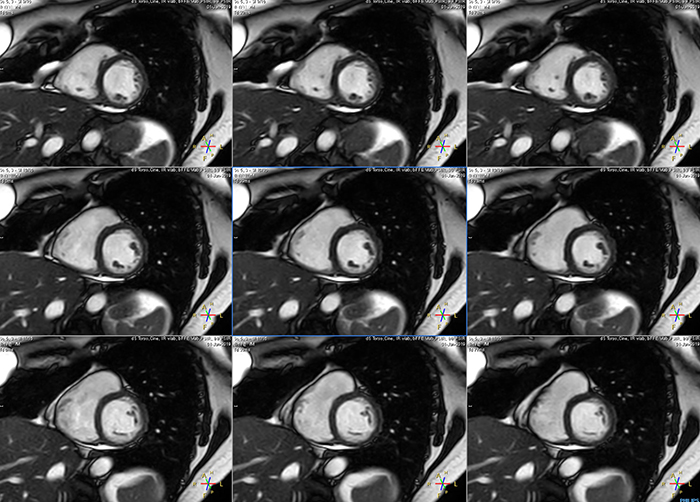

Short breath hold cardiac cine

These are some images of a cardiac cine scan with a short breath-hold time. A high temporal resolution provides a smooth cine, which helps in assessing heart function. Ingenia Ambition.

"The ability to adjust Compressed SENSE to enable shorter breathholds translates to a much smoother cine”

Avila says that Compressed SENSE allows them to reduce breathhold time to 3 to 4 seconds in cardiac cine scans. “At the same time, we can now – based on cardiac frequency – obtain as many as 30 to 40 cardiac phases without sacrificing resolution, while before Ingenia Ambition, we were acquiring only 20 phases.

“This ability to use Compressed SENSE for obtaining higher temporal resolution translates to a much smoother cine. This allows me to better assess heart function,” Dr. Peña says.